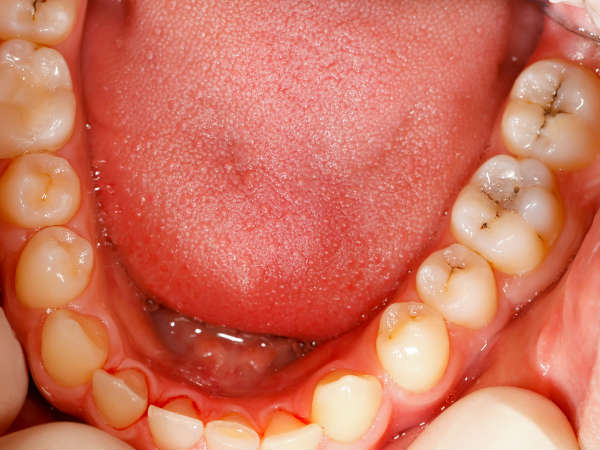

உங்க வாயில் இந்த பகுதிகளில் எல்லாம் புற்றுநோய் வருமாம்... இந்த அறிகுறிகள் இருந்தா அசால்ட்டா இருக்காதீங்க!

Oral Cancer In Tamil: வாய் புற்றுநோய் என்பது வாயின் எந்தப் பகுதிகளிலும் உருவாகும் புற்றுநோயைக் குறிக்கிறது. நாக்கு, வாய் மற்றும் ஈறுகளில் உள்ள திசு, நாக்கின் கீழ், நாக்கின் அடிப்பகுதி மற்றும் வாயின் பின்புறம் மற்றும் மேல்புறம், தொண்டைப் பகுதி ஆகியவற்றில் வாய்வழி புற்றுநோய்கள் உருவாகின்றன.

ஸ்குவாமஸ் செல் கார்சினோமா என்பது வாய் புற்றுநோயின் மிகவும் பொதுவான வகையாகும். இது 10 வழக்குகளில் ஒன்பது நிகழ்வுகளுக்குக் காரணமாகிறது. வாயின் உட்புறம் மற்றும் தோலின் கீழ் உட்பட உடலைச் சுற்றியுள்ள பல இடங்களில் செதிள் செல்கள் காணப்படுகின்றன. வாய் புற்றுநோய் தொடங்கக்கூடிய குறிப்பிட்ட பகுதிகள் மற்றும் ஒவ்வொன்றின் அறிகுறிகளையும் பற்றி இக்கட்டுரையில் தெரிந்துகொள்ளலாம்.

வாய் புற்றுநோய்

புகையிலை பொருட்களைப் பயன்படுத்துதல் மற்றும் தொடர்ந்து அதிக மது அருந்துதல் ஆகியவை உங்கள் வாயின் தரையில் புற்றுநோயை உருவாக்கும் வாய்ப்புகளை அதிகரிக்கும். இந்த வகை புற்றுநோயின் பொதுவான அறிகுறி வாயில் ஒரு புண் ஏற்படுவது. அந்த புண் பெரிதாக வளர்ந்து கொண்டே போகும். மற்ற அறிகுறிகளில் வாயில் வெள்ளை, சிவப்பு அல்லது இருண்ட திட்டுகள் ஏற்படுவதும், வாய் வலி மற்றும் கழுத்தில் கட்டி ஏற்படுவதும் ஆகும்.

ஈறு புற்றுநோய்

இந்த வகை புற்றுநோய் மேல் அல்லது கீழ் ஈறுகளில் தொடங்குகிறது. இதற்கான அறிகுறிகள் ஈறுகளில் வெள்ளை, சிவப்பு அல்லது கருமையான திட்டுகள் ஏற்படுவது. மேலும், ஈறுகளில் இரத்தப்போக்கு அல்லது வெடிப்பு ஏற்படுவதும் ஈறு புற்றுநோயின் அறிகுறிகளாகும். இந்த அறிகுறிகள் உங்களுக்கு தென்பட்டால், உடனே மருத்துவரை அணுகுவது நல்லது.

அண்ணம் புற்றுநோய்

பிளேட் என்பது வாயின் உட்புறத்தின் மேற்பகுதி. இது அண்ணம் அல்லது மேல்வாய் என்று அழைக்கப்படுகிறது. உட்புற வாயின் மேல்பகுதியில் எலும்புப் பகுதியை உருவாக்கும் செல்கள் கட்டுப்பாட்டை மீறி வளர்ந்து, புண்கள் அல்லது கட்டிகளை உருவாக்கும் போது கடினமான அண்ண புற்றுநோய் தொடங்குகிறது. இதன் பொதுவான அறிகுறி வாயின் மேற்பகுதியில் ஏற்படும் புண் ஆகும். புற்றுநோய் வளரும் போது, அந்த புண்ணில் இருந்து இரத்தம் வெளிவரலாம்.

நாக்கு புற்றுநோய்

உங்கள் நாக்கில் இரண்டு பகுதிகள் உள்ளன. வாய்மொழி மற்றும் நாக்கின் அடிப்பகுதி. புற்றுநோய் எந்த பகுதியில் வேண்டுமானாலும் உருவாகலாம். நாக்கு புற்றுநோயின் அறிகுறிகள் பின்வருமாறு:

- நாக்கில் சிவப்பு, வெள்ளை அல்லது கருமையான திட்டுகள்

- தொண்டை புண்

- நாக்கில் ஒரு புண் அல்லது கட்டி ஏற்படுவது

- உணவு விழுங்கும் போது வலி

- வாய் உணர்வின்மை

- நாக்கில் இருந்து ரத்தம் வழிவது

- நாக்கில் இருக்கும் புண்ணில் இருந்து இரத்தம் வழிவது